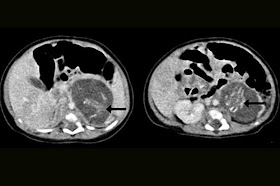

Os outros dois bebês foram extraídos cirurgicamente e especialistas estimam que eles estavam entre a oitava e décima semana de gestação. Segundo a publicação médica, eles apresentavam quatro membros, pele intacta, costelas, genitália ambígua, espinha, intestinos, ânus e tecido cerebral. Embora o caso ainda esteja sendo investigado, a menina recém-nascida teve uma boa recuperação e recebeu alta do Hospital Yau Ma Tei oito dias após a operação. Fonte:Diariodepernambuco